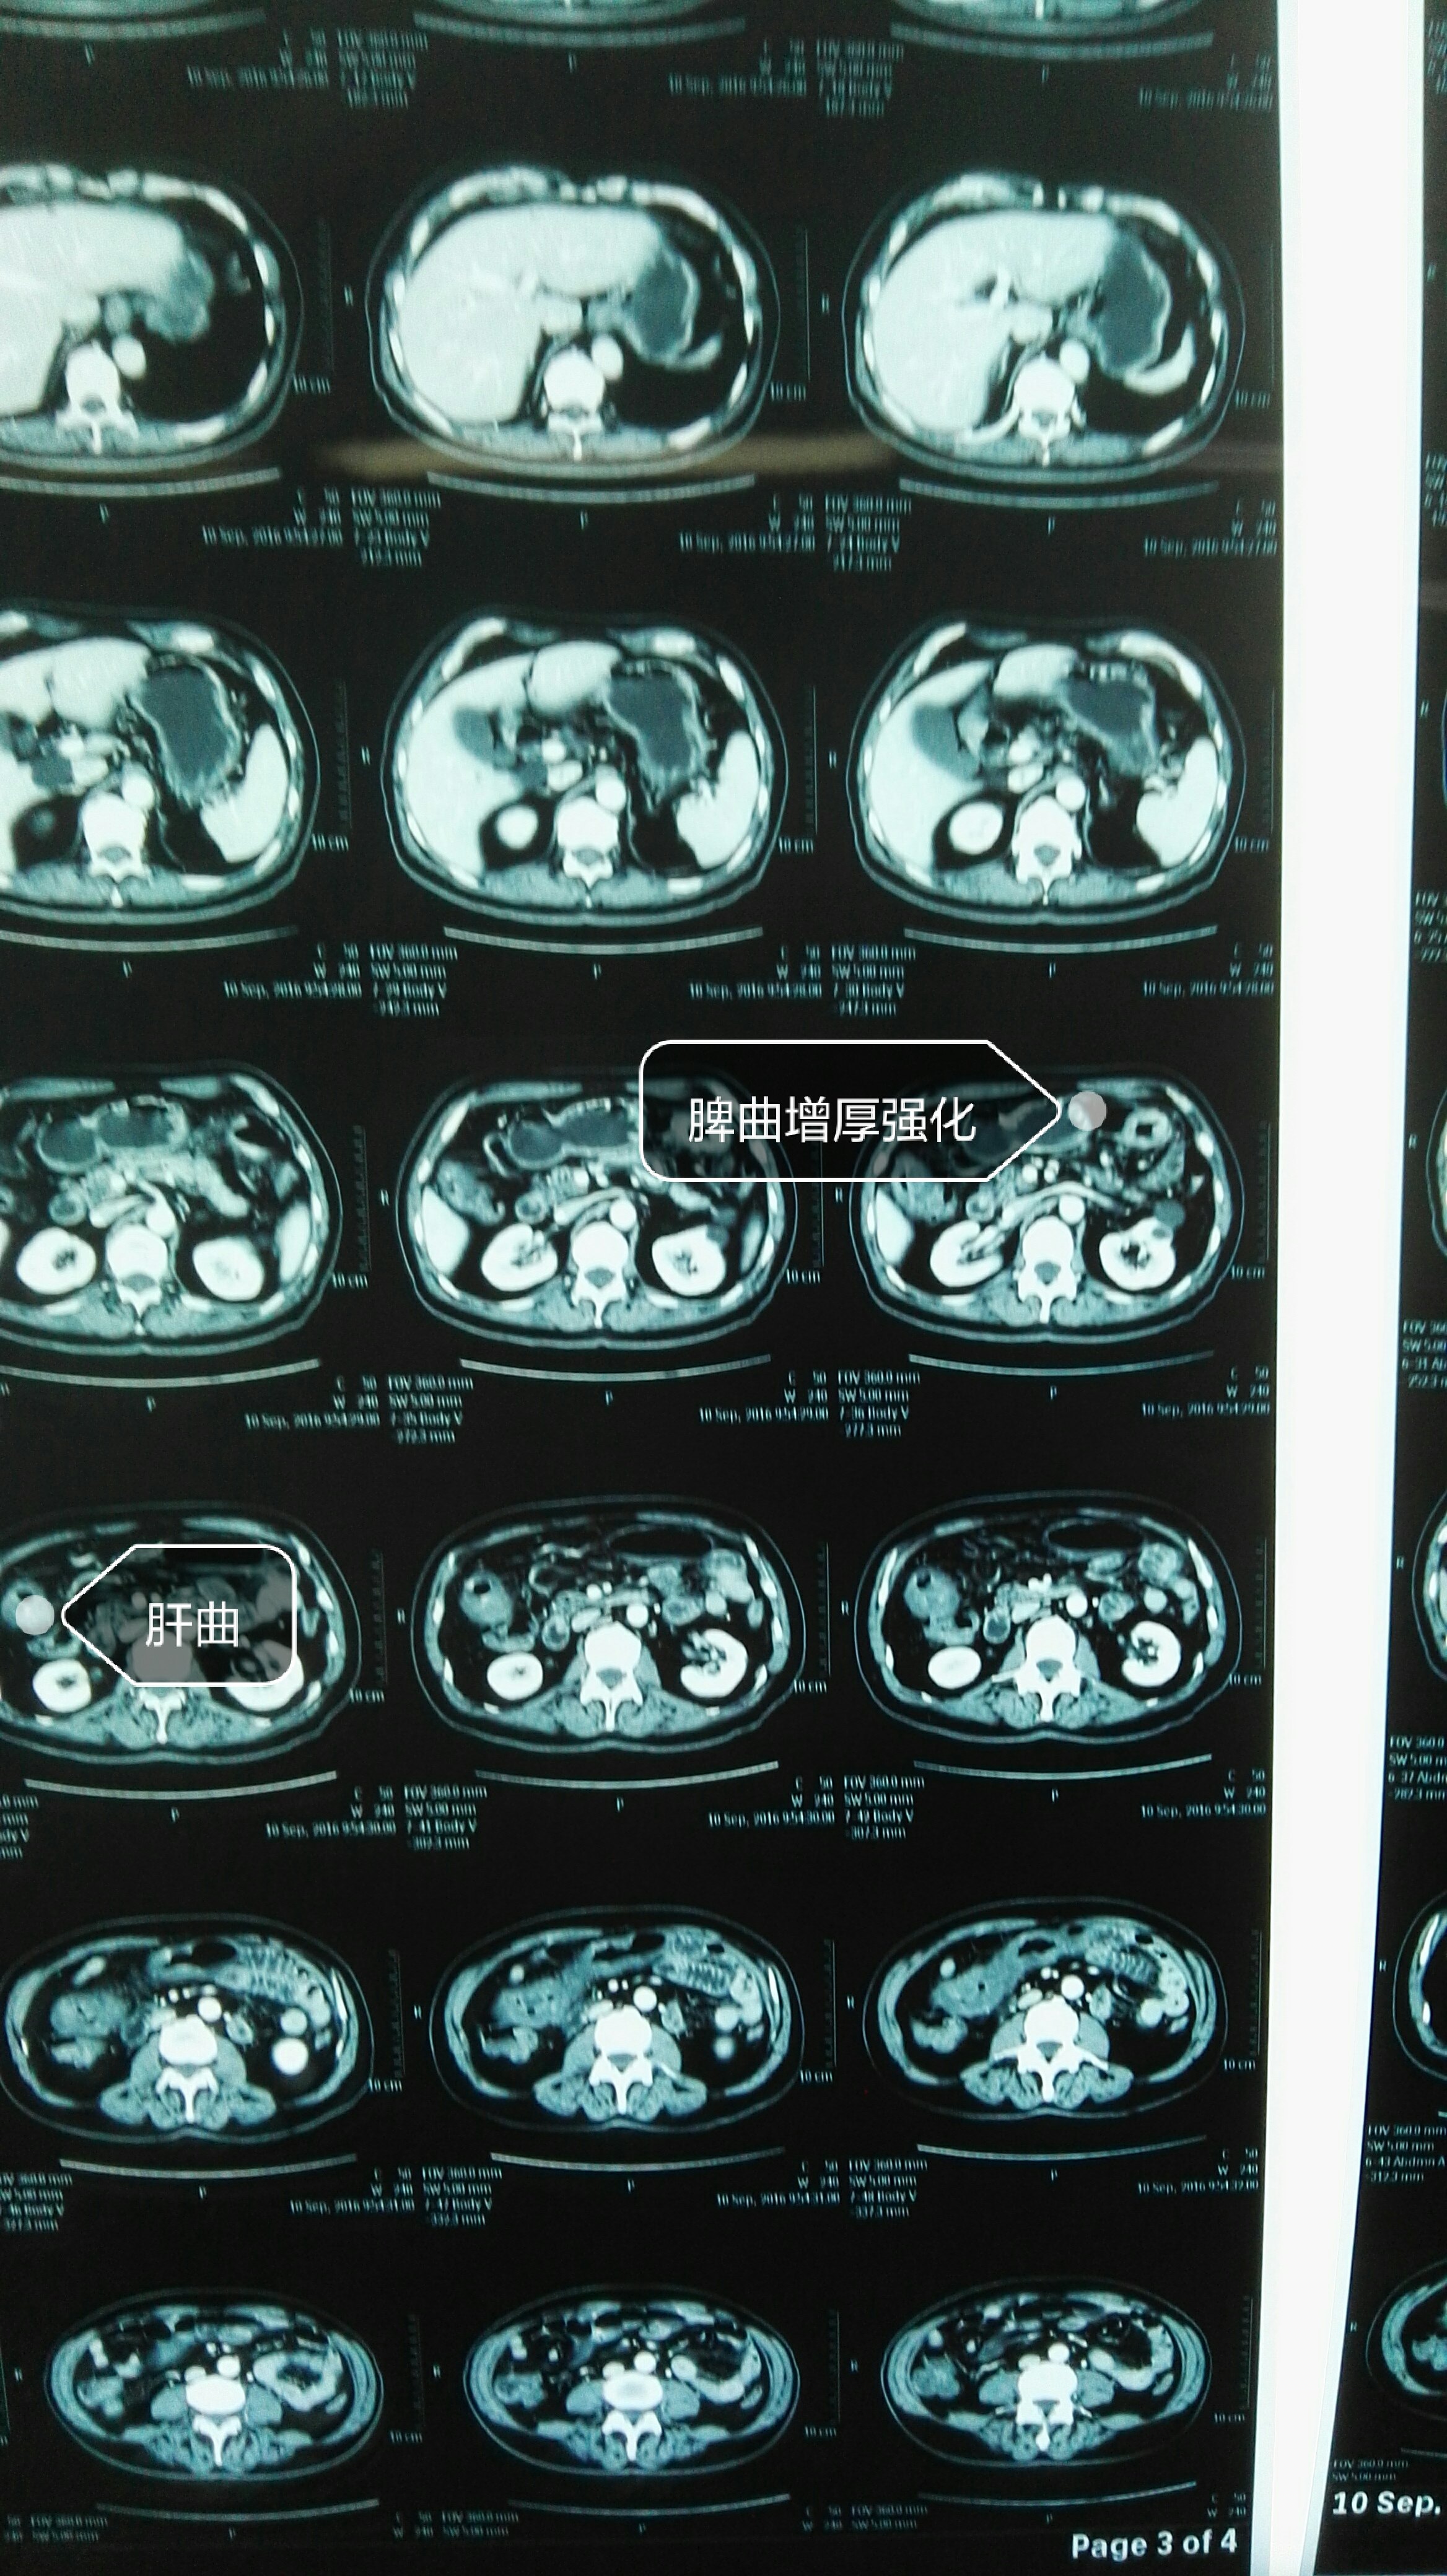

外一 张瑞林 病情汇报

就医后ct检查显示:文先生的结肠肝曲局部增厚,肠腔狭窄,伴结肠梗阻,有

经肠镜定位发现,患者的肿瘤位于横结肠肝曲段,周围脂肪间隙数可见淋巴

部分横结肠(超过二分之一)及其完整系膜,手指处为结肠肝曲缩窄性包块